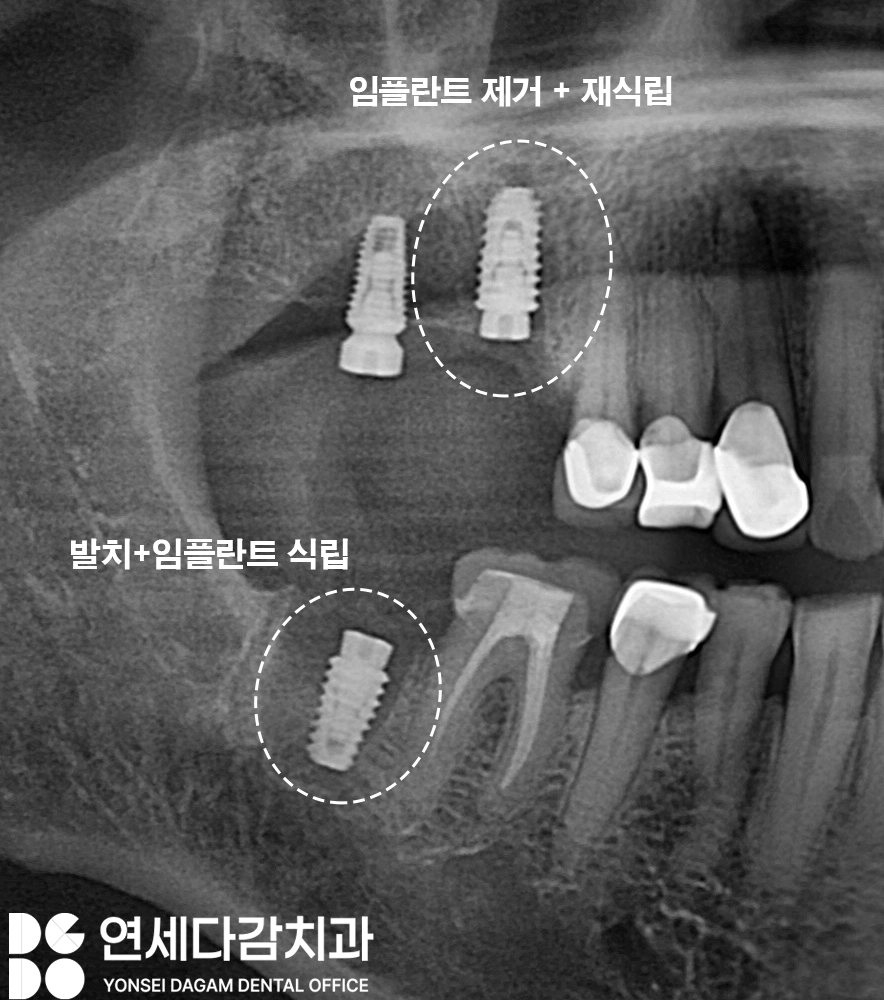

기존에 임플란트가 식립되어 있던 부위의

보철이 부러지는 문제가 생기기도 하죠.

가락시장역 치과 에서는 이런 복합적인

상황을 체계적으로 접근하는 것을

중요시 여깁니다.

파절된 임플란트 보철을 제거하고

임플란트 본체의 상태를 확인해 봤을 때

상부 보철과 연결되는

부위가 부러져 있는 것을

볼 수 있습니다.

치근 우식이 심했던 부위도

발치하여 즉시 임플란트 식립을

시행하게 됩니다.

이렇게 이가 나온 자리에

즉시 식립하면,

발치와의 치유력을 이용하여

더욱 원활한 재생 능력으로

빠른 골 유착을 도모할 수 있습니다.

임플란트와 뼈가 빠르게 유착되어

고정력을 확보하면

나머지 단계도 빠르게 진행되어

최종 단계까지

기간을 단축하게 됩니다.